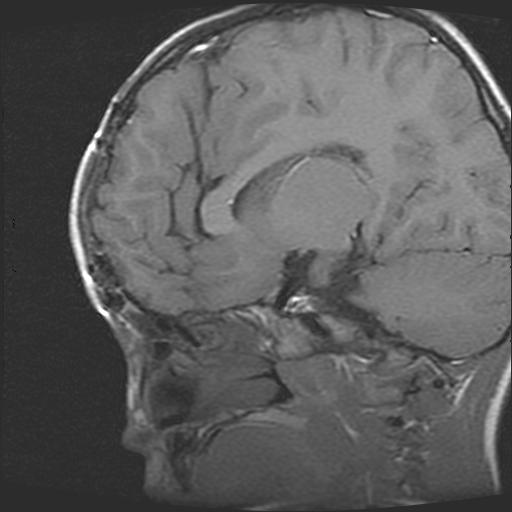

标题: PED0377: 6岁小儿,左侧视神经瘤术后

6岁小儿,左侧视神经瘤术后。现左侧视力减退。